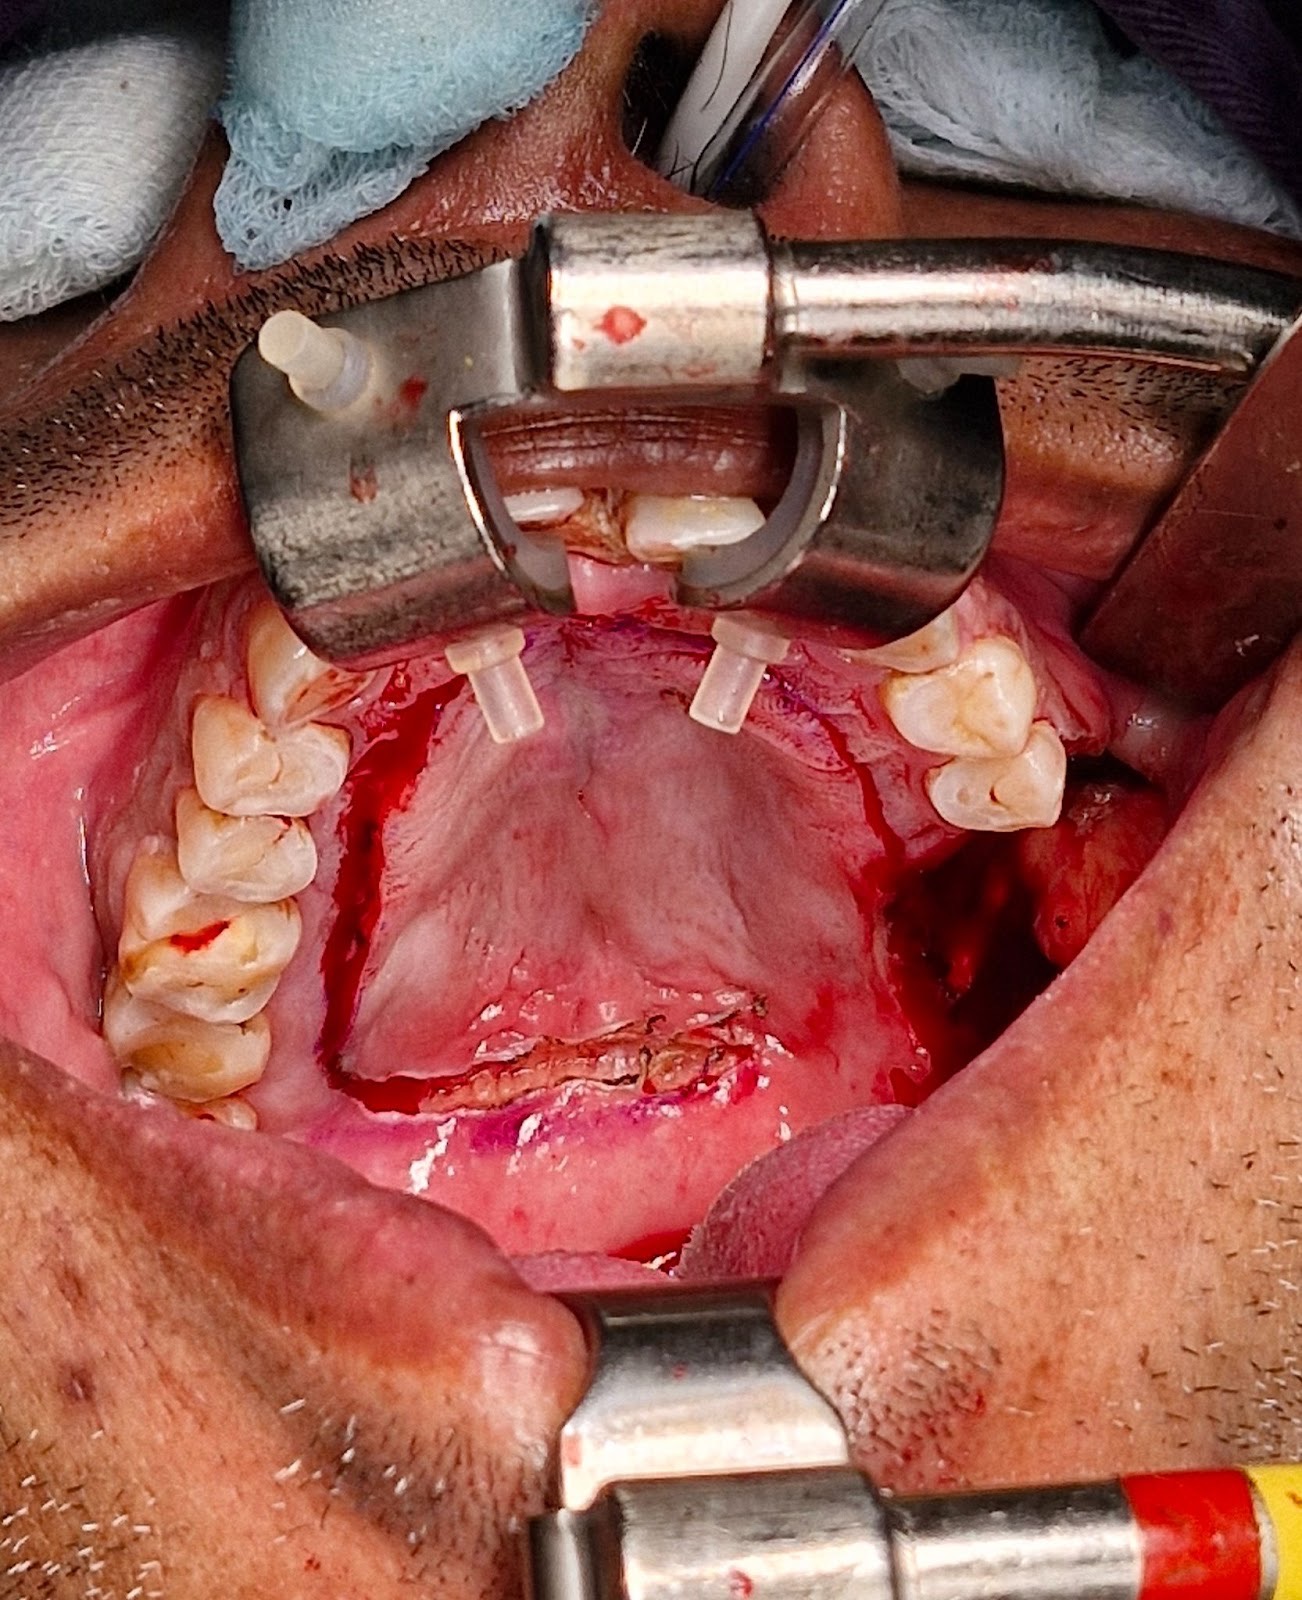

The biopsy proven tumor (SCC) at left retromolar trigione was excised with adequate margins resulting in a defect approximately 3 x 2.5 cm. A sterile marker was used to mark the incisions sparing 5 mm of attached mucoperiosteum. Incision was placed using # 15 blade upto the bone depth and mucoperiosteal flap was raised starting from the contralateral side and towards the vascular pedicle. Posterior releasing incision is made to release the flap for tension free rotation into the defect. Once adequately released, the flap is rotated to cover the defect and secured using Vicryl 4-0 suture. The donor site exposed bone was covered with White Head Varnish (WHV) pack and secured in place using prolene 3-0 suture.